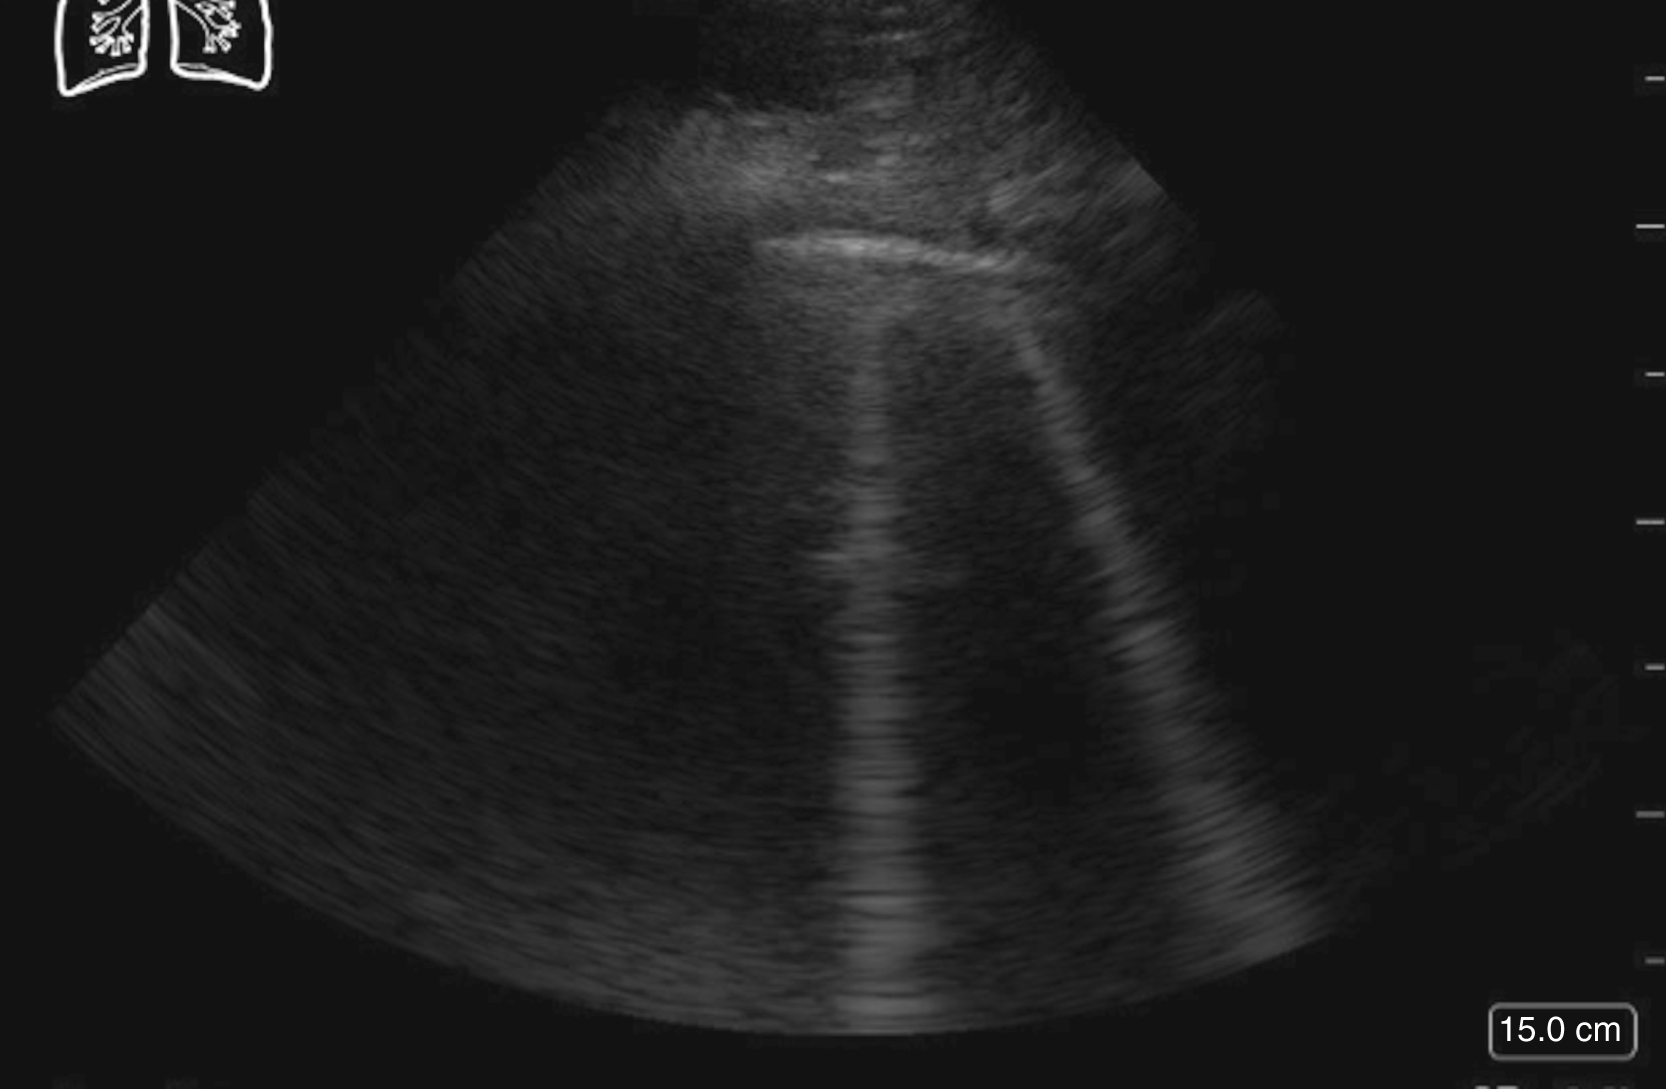

The visualization of lung sliding excludes the presence of a pneumothorax at that location on the patient’s chest wall. Although M-mode and color Doppler techniques have been described as adjuncts to the evaluation of patients with suspected pneumothorax, neither is a necessary component of the examination. Absent lung sliding can result from a variety of causes in addition to pneumothorax, including pleural adhesions or consolidations, blebs, pleurodesis, partial or complete pneumonectomy, and contralateral mainstem bronchus intubation ( Fig. e3.15 ). A lung point sign is identified at the border of the pneumothorax, where the image shows absent lung sliding until the lung moves into the interspace with respiration ( Video e3.12 ).

M mode images of the lung. (A) Normal lung with “seashore” sign. (B) Pneumothorax with “stratosphere” or “barcode” sign.